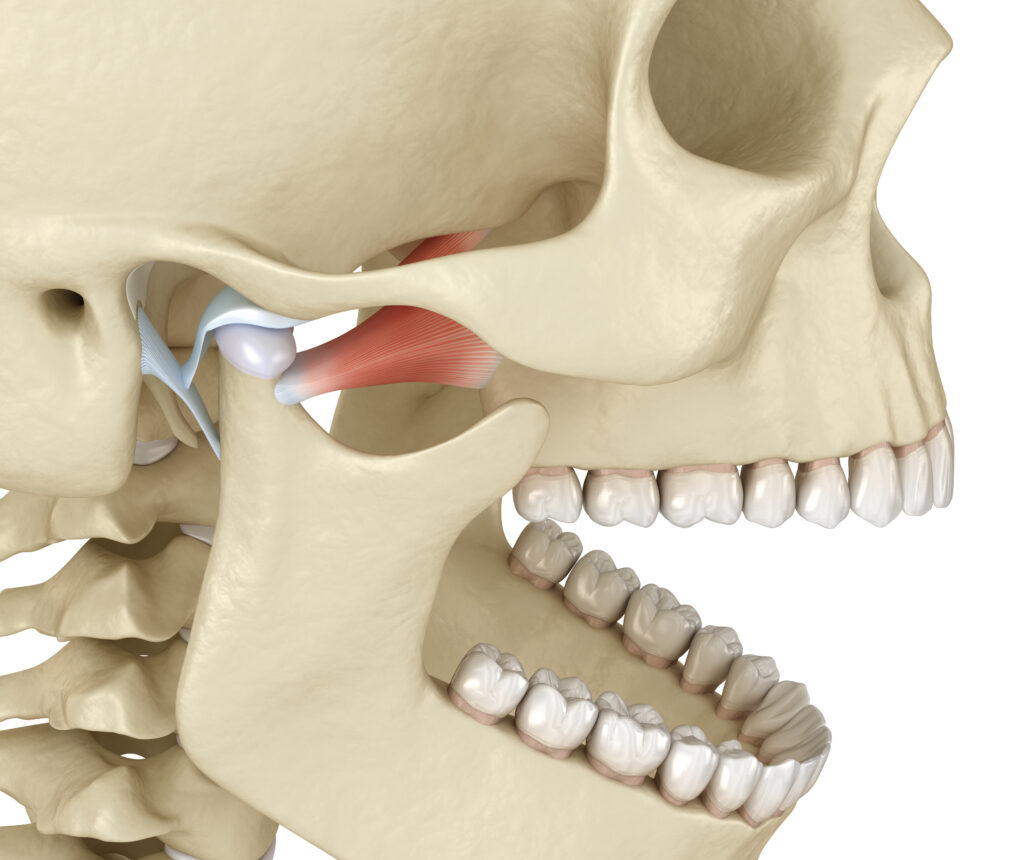

Dental X-rays to examine your teeth and jaw. CT scan to provide detailed images of the bones involved in the joint. MRI to reveal problems with the joint’s disk or surrounding soft tissue. TMJ arthroscopy is sometimes used in the diagnosis of a TMJ disorder. During TMJ arthroscopy, your doctor inserts a small thin tube (cannula) into the joint.. If the problems are severe, linger, or get worse, the doctor or dentist can refer a patient to one of the various specialists who deal with TMJ disorders. Specialized treatment providers include: An oral and maxillofacial surgeon, trained to handle a variety of diseases, injuries, and defects of the head, neck, mouth, jaw, and face.

Since 1936 TMJ has been primarily treated by dentists, however today, we know TMJ to be a complex condition with many biological systems (circulatory, digestive, endocrine, exocrine, immune, muscular, nervous, reproductive, respiratory, and skeletal) playing a role, indicating the need to bring the medical and other allied health professionals in research and patient care.. Dr. Demerjian Center For TMJ And Sleep Therapy. Burbank: (818) 238-9865 | Glendora: (626) 852-1865. 2701 W Alameda Ave. #606, Burbank CA 91505. 175 N. Pennsylvania Ave. #4, Glendora CA 91741.